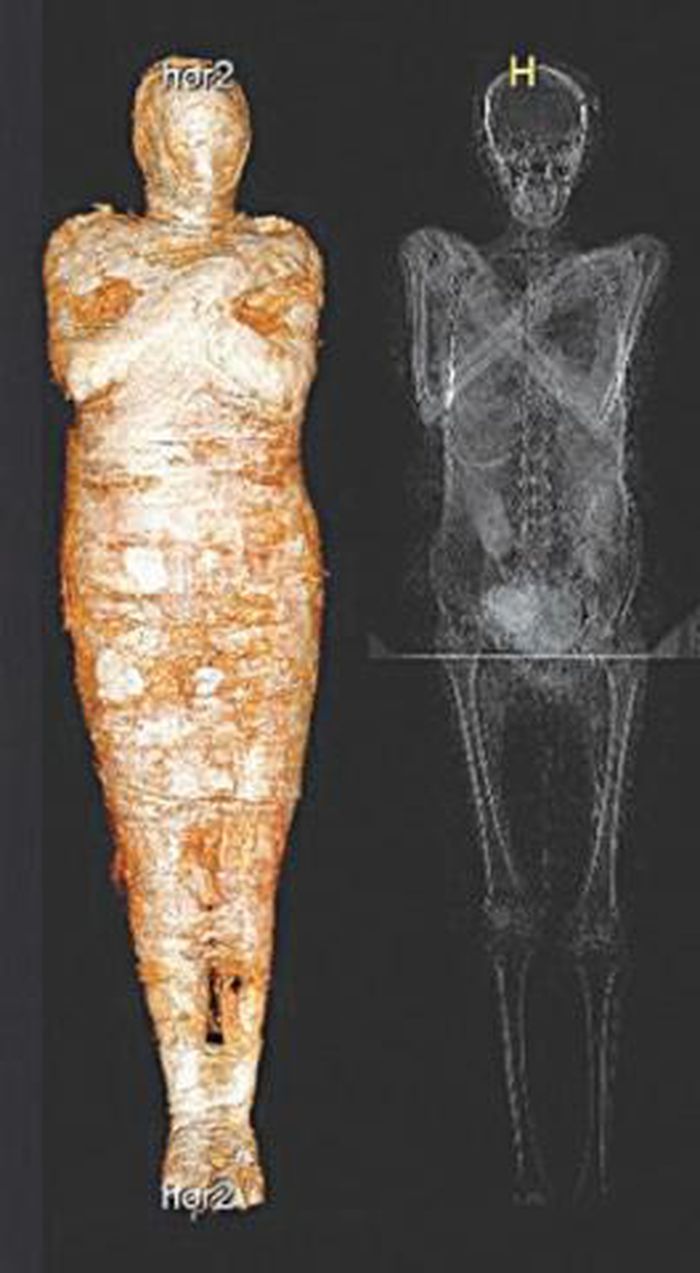

Được lưu giữ trong Bảo tàng Quốc gia ở Warsaw, Ba Lan từ năm 1917, một xác ướp Ai Cập cứ ngỡ thuộc về linh mục nhưng thực tế là của một thai phụ.

Vào năm 1826, một xác ướp Ai Cập và quan tài được tặng cho Đại học Warsaw, Ba Lan. Sau đó, chúng được lưu giữ và bảo quản trong Bảo tàng Quốc gia ở thành phố Warsaw kể từ năm 1917.

Theo các chuyên gia, xác ướp có niên đại hơn 2.000 năm tuổi. Trong suốt nhiều năm, họ cứ ngỡ đó là thi hài của một linh mục Ai Cập cổ đại tên là Hor-Djehuty.

Tuy nhiên, bí mật "động trời" về giới tính của xác ướp trên được hé lộ khi các chuyên gia sử dụng kỹ thuật chụp cắt lớp vi tính vào năm 2016.

Kết quả cho thấy xác ướp không phải là của linh mục Hor-Djehuty. Thay vào đó, thi hài thuộc về một phụ nữ tử vong khi mang thai. Thai nhi đang ở tuần thai thứ 26 - 30.

Thai phụ này được ướp xác rất cẩn thận với một bộ bùa hộ mệnh. Điều này cho thấy bà xuất thân từ tầng lớp giàu có hoặc có địa vị cao trong xã hội.

Các nhà nghiên cứu tin rằng việc phân tích các mô mềm được bảo quản của xác ướp có thể mang lại một số manh mối giúp tìm ra nguyên nhân tử vong của thai phụ.

Dù vậy, một số chuyên gia đưa ra giả thuyết người phụ nữ có thể đã gặp một số vấn đề về sức khỏe trong quá trình mang thai. Điều này khiến bà tử vong trong thời gian thai kỳ.